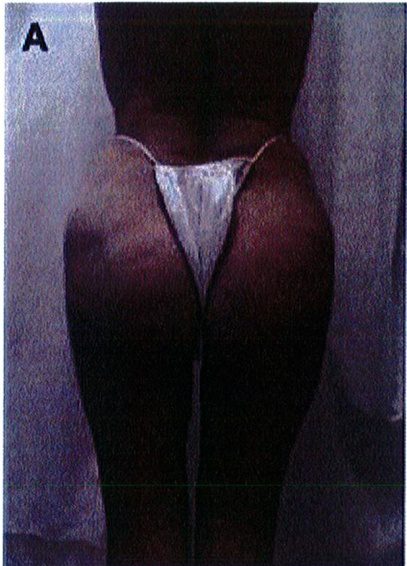

Những bệnh nhân có mào chậu rộng, khung chậu hẹp và ngắn hoặc sa hay thiếu mô mềm ở mông sẽ không phù hợp với các thủ thuật nâng mông, bất kể áp dụng ở mặt phẳng nào. Các tác giả khuyến cáo họ nên chuyển sang phương pháp ghép mỡ (Hình 2).

Hình. 2. Bệnh nhân với khung chậu quá rộng hoặc quá ngắn đều không phù hợp với implant mông.